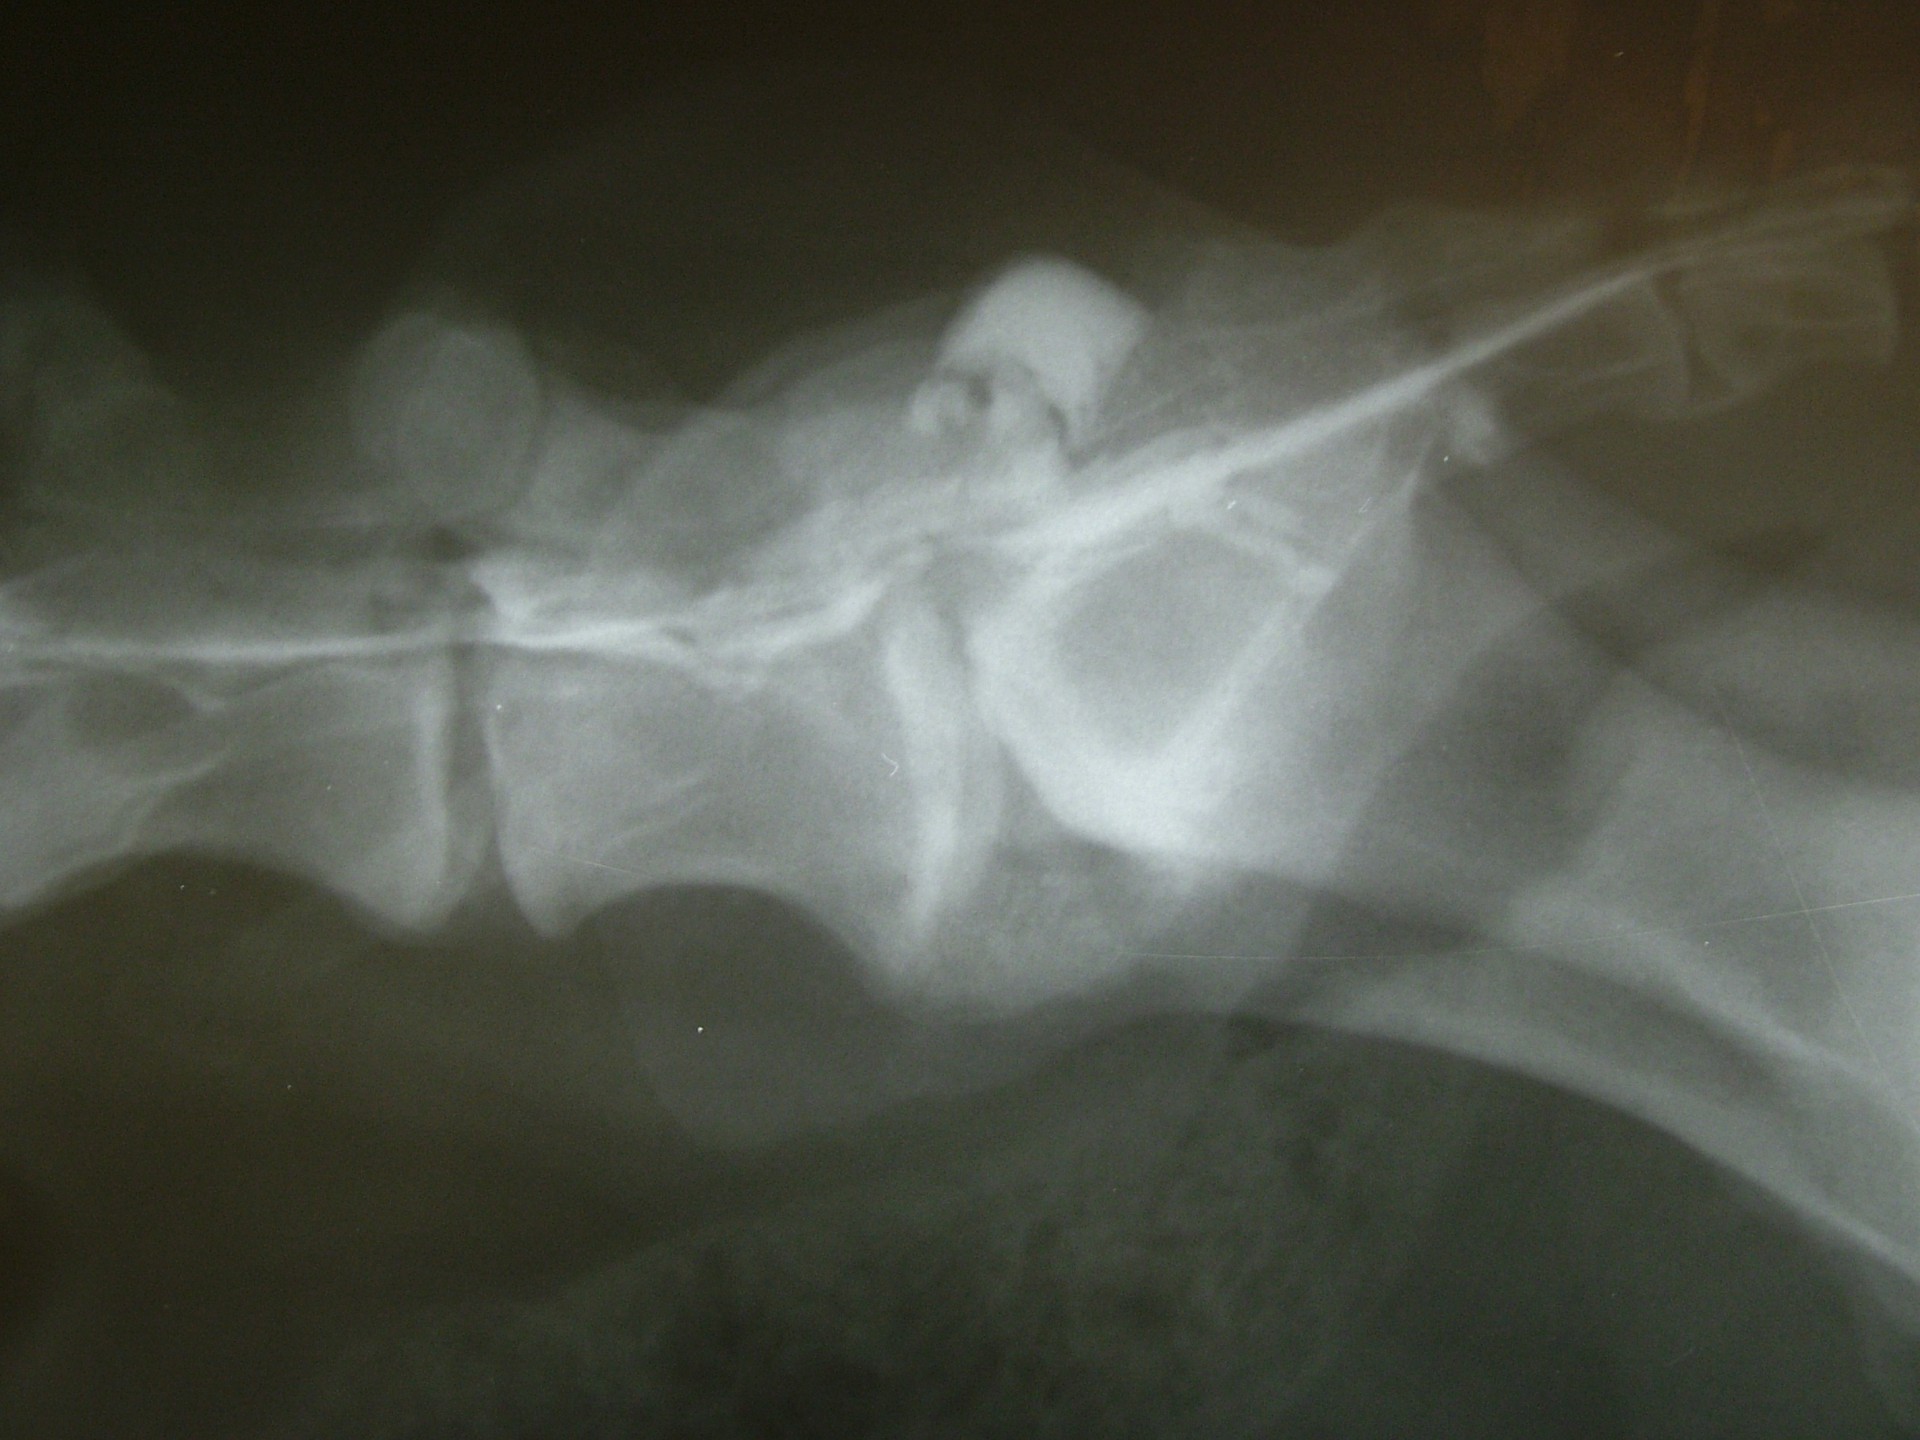

A C.E.C diagnosztikájának legfontosabb lépése a kórelőzmény megismerése után (hátulsó testfél gyengeség, rogyadozás, széklet-vizeletürítési problémák, fájdalom stb.) az alapos klinikai vizsgálat, mely során a gerinctájék fájdalmasságát, a hátulsó végtag reflexeit, a fájdalomérzet meglétét vizsgáljuk.Amennyiben a klinikai tünetek indokolják kiegészítő vizsgálatként elsősorban a röntgenvizsgálat jön szóba, mely során a gerincoszlop ezen szakaszáról oldalirányú felvételt készítünk.

Amennyiben a klinikai tünetek és az oldalirányú röntgenfelvétel alapján a C.E.C. alapos gyanúja felmerül további vizsgálatokkal kell kizárnunk egyéb gerincbetegségeket ill. megerősíteni a C.E.C. diagnózisát.

Az egyik ilyen vizsgálat a gerincfestés vagy myelographia, mely során a gerincvelőt körbevevő térbe (subduralis tér), az agy-gerincvelői folyadékba (liquor) röntgenkontraszt anyagot juttatunk és sorozatos felvételekkel ellenőrizzük annak áramlását. Ennek előnye, hogy a kontrasztanyag lefutása során az egyéb gerincszakaszok is kirajzolódnak, és ezek esetleges betegségeit is diagnosztizálhatjuk. A gerincoszlop hátsó szakaszáról 1db teljesen hajlított és 1 db teljesen nyújtott beállítású RTG felvételt készítünk. Ha a két felvétel között jelentős különbséget tapasztalunk a C.E.C. biztosan diagnosztizálható.A másik invazív diagnosztikai eljárás a durographia, mely során a röntgenkontraszt anyagot a durazsák körüli térbe (epiduralis tér) juttatjuk és így indirekt módon ábrázoljuk a gerincvelő esetleges összenyomatását. A vizsgálat során a kontrasztanyag telődési hiánya jelzi az összenyomatást és annak mértékét.A diagnosztika legmodernebb vizsgálati módszere az MRI vizsgálat, mely során altatásban, invazív beavatkozás nélkül kaphatunk átfogó képet a vizsgálni kívánt gerincszakaszról. Magyarországon állatorvosi diagnosztikai célra csak a Kaposvári Egyetem Diagnosztikai és Onkoradiológiai Intézetében működő berendezés használható.